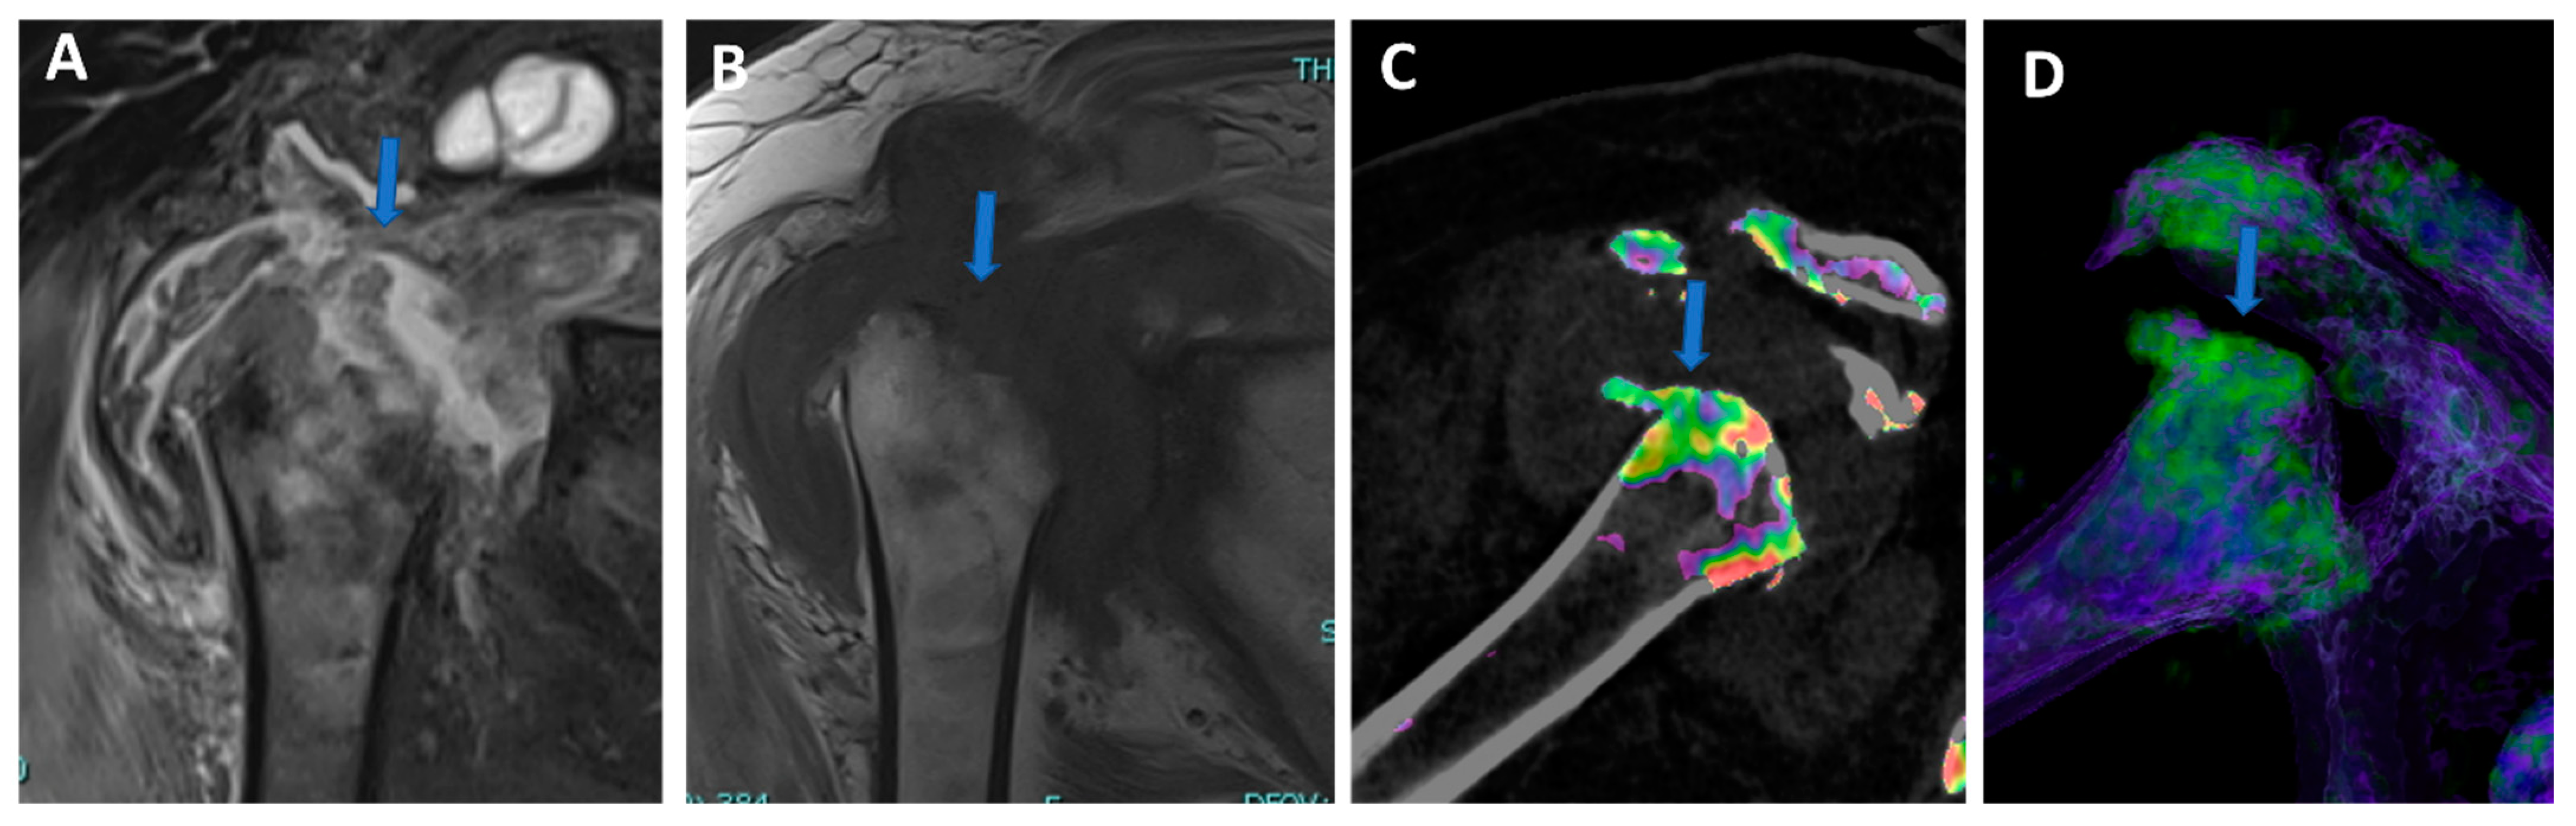

Figure 7. Shoulder acute crystal arthritis. On coronal STIR and T1 weighted MR images (A,B), it is possible to identify erosive changes and BME of the humeral head (arrow) with corpuscular fluid within the articular cavity. On para-coronal 2D and 3D DECT images (C,D), severe bone reabsorption with edema of the femoral head is confirmed (arrow).

In clinical practice, BME maps reconstructed from VNCa imaging could be employed to detect bone marrow lesions around the imaged joints. Although iodinated contrast material could generate some artifacts in the adjacent areas, the presence of BME can still be visualized. For example, in the case of shoulder trauma with doubtful dislocation, the presence of BME on the posterior aspect of the humeral head may help corroborate the diagnosis of a Hill-Sachs lesion (Figure 1 and Figure 6). In addition, BME around the joint, with or without erosions, can be found in inflammatory diseases such as septic or aseptic arthritis [31,32,33] (Figure 7).